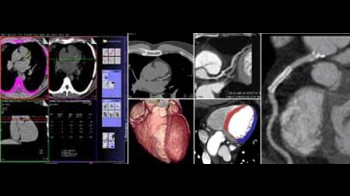

Koronarna CT angiografija

Kardiovaskularne bolesti su ubica broj jedan u današnjem svijetu i odnose svake godine više života nego sve maligne bolesti zajedno. Koronarna bolest je najčešće uzrokovana aterosklerozom (stvaranjem plakova u zidu krvnih žila uzrokojući njihvo suženje). Donedavno, nije postojao neinvazivni način da se direktno analiziraju koronarne arterije na prisustvo aterosklerotskih promjena. Razvoj tehnologije višeslojnog CT-a (MSCT/MDCT) omogućio je detaljno trodimenzionalno prikazivanje kucajućeg srca u toku jednog zadržavanja daha. U našem dijagnostičkom centru nudimo ovu tehniku pregleda koronarnih arterija, na multi-slice aparatu, s najmodernijim softverom i minimalnom dozom zračenja.

Šta je CT koronarografija?

To je metoda prikaza malih arterija koje hrane  srčani mišić, upotrebom CT skenera, koji prikazuje protok krvi u koronarnim arterijama i kompjuterskog softvera da bi se dobio odgovarajući trodimenzionalni prikaz. CT angiografija je neinvazivni način da se prikažu zidovi koronarnih arterija I nadju eventualni aterosklerotski plakovi, što pomaže liječniku u odredjivanju rizika srčanog udara.